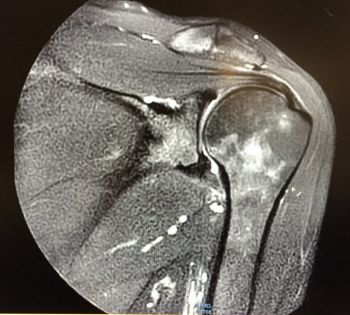

Considérée comme l'une des techniques de pointe en matière d'imagerie médicale, l'IRM ( imagerie par résonnance magnétique) permet souvent un diagnostic précis pour bon nombre de pathologies.

En associant le magnétisme et des ondes radio-fréquences, l'IRM permet de réaliser des images très précises.

Pratiquement toutes les indications, l'IRM est notamment l'examen de prédilection pour toutes études neurologiques.